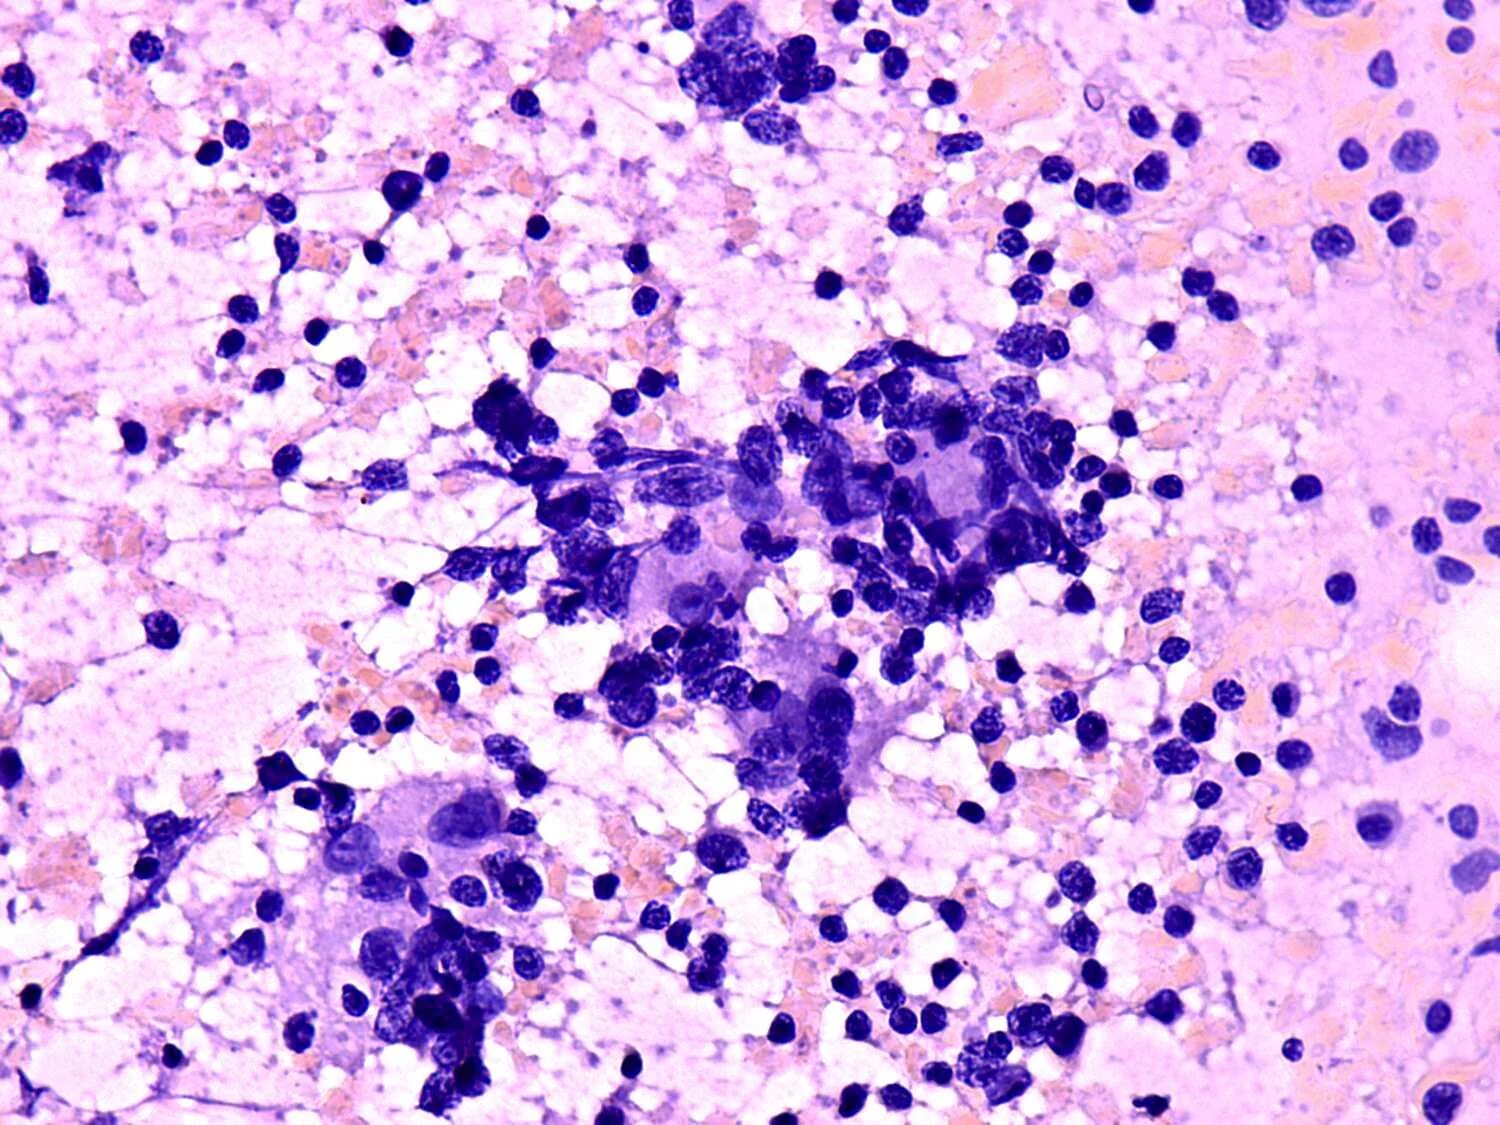

Выраженная атипия